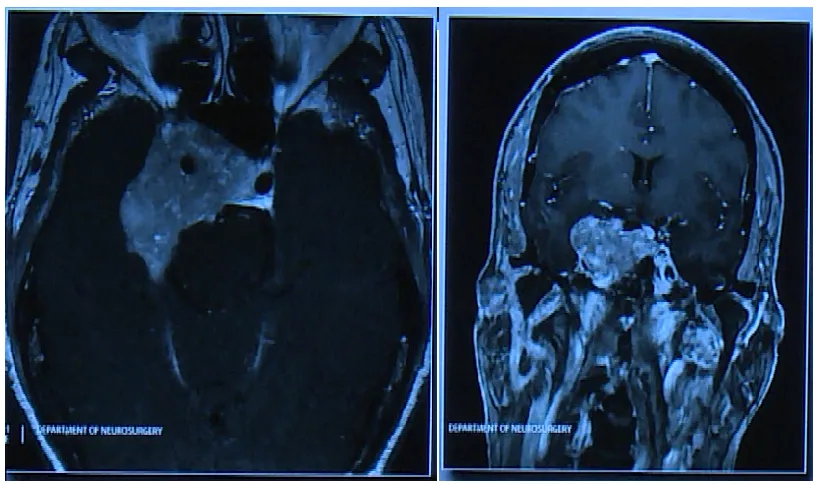

Couldwell教授演講中展示的部分巨大垂體瘤